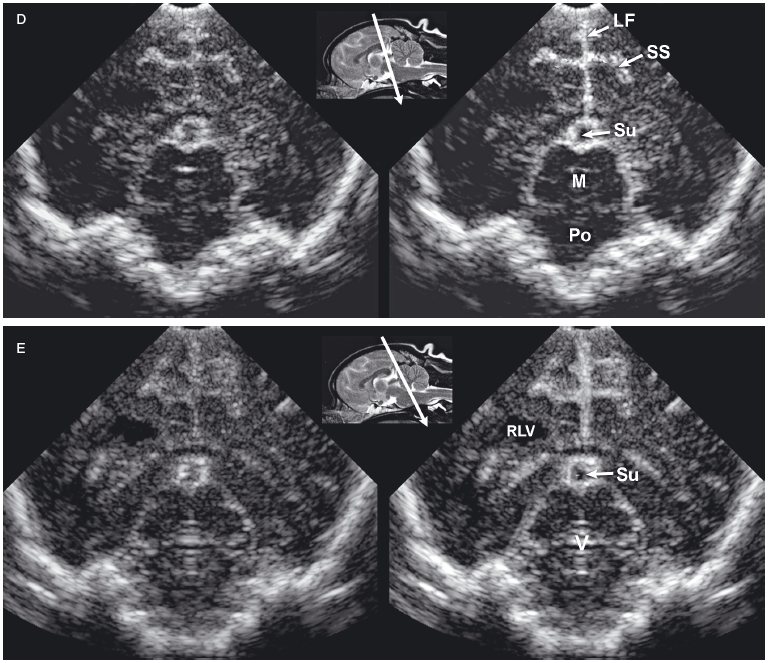

Figure 1.3. Transverse sonograms of the brain of a 1-month-old Yorkshire terrier. The ventricles are asymmetrical but within normal limits. A: Rostral sonogram. B: Sonogram at the level of the interthalamic adhesion. C: Sonogram at the level of the third ventricle. D: Sonogram with the ultrasound beam angled caudally to image the mesencephalon. E: Sonogram with the ultrasound beam angled caudally to image the cerebellum. 3, third ventricle; CC, corpus callosum; CG, cingulate gyrus; CN, caudate nucleus; F, fornix; H, hippocampus; IA, interthalamic adhesion; LF, longitudinal fissure; LLV, left lateral ventricle; M, mesencephalon; P, pyriform lobe; Po, pons; RLV, right lateral ventricle; SS, splenial sulcus; Su, subarachnoid space; T, thalamus; and V, vermis.

As the beam is swept slightly more caudally, the rostral fornix comes into view. Choroid plexus is hyperechoic while it lies on the floor of the central portion of the lateral ventricle and the roof of the temporal horn. It may be difficult to distinguish between the caudate nucleus and the adjacent choroid plexus in the lateral ventricle, so only a single hyperechoic focus might be seen on each side of the midline in some dogs. If there is sufficient CSF, the lateral ventricle can be seen.

In older puppies and adult dogs, alternating hyperechoic and hypoechoic lines represent the callosal sulcus, corpus callosum, and fornix. Comparison with histological samples suggests that the most superficial hyperechoic layer is the callosal sulcus, which contains vessels that pulsate. The corpus callosum is comprised of a hypoechoic surface with a deeper hyperechoic border. The fornix is hypoechoic. In the first few days of life, these structures may appear only as a single hyperechoic region. Detail improves as myelination progresses after birth. Most of the brain is uniformly hypoechoic, but the pyriform lobes are visible because of hyperechoic meninges dorsal to each lobe.

When the probe is tilted to sweep the ultrasound beam caudally, the dorsal portion of each hippocampus appears as a hypoechoic structure close to the midline. Dorsolateral to each of these structures, a hyperechoic area represents choroid plexus in each lateral ventricle. Another hyperechoic area is seen in the midline ventral to the level of the dorsal portions of the hippocampi. Depending on the angle of ultrasound section, this hyperechoic area may represent choroid plexus in the dorsal portion of the third ventricle or pia mater that is located more caudally in the adjacent subarachnoid space. Vessels and trabeculae in the subarachnoid space may create a complex of echoes that outline the mesencephalon and cause it to appear as a dome-shaped hypoechoic structure. The petrous temporal bones will create irregular hyperechoic echoes on the floor of the cranium on each side of the midline deep to the hypoechoic pyriform lobes.

More caudally, the osseous tentorium is a hyperechoic structure shaped like an inverted V. In older animals, this structure often prevents visualization of the caudal brain, but the medulla and cerebellum can be imaged in neonatal animals. The medulla is hypoechoic. The vermis of the cerebellum is represented by a stack of hyperechoic lines seen in the midline. Each lateral cerebellar hemisphere is located more laterally as a hypoechoic structure.

Longitudinal images made near the midline are true sagittal images, but when the probe is moved past the edge of the fontanel, the probe must be angled to enable the beam to reach the lateral margins of the brain. The floor of the cranium appears curved in images showing the lateral portions of the brain, whereas the floor of the cranium is more irregular in images made near the midline (midsagittal images). As the probe is angled laterally, structures that are anatomically closer to the midline appear in the near field of the ultrasound image, whereas more lateral structures are seen in the far field (Figure 1.4).

The interthalamic adhesion and, more caudally, the mesencephalon can be seen in midsagittal images as hypoechoic structures surrounded by echoes created mainly by choroid plexus in the third ventricle and meninges and in vessels in the subarachnoid space. In some areas, the third ventricle will appear anechoic or hypoechoic because of the presence of CSF. The osseous tentorium is incompletely ossified in neonates, enabling visualization of hyperechoic echoes created by the vermis in the posttentorial area of the brain. More superficially, the callosal sulcus is seen as a hyperechoic line. The corpus callosum has an appearance similar to that seen in transverse images. It is hypoechoic, with a deep hyperechoic interface.

When the probe is angled to obtain a lateral parasagittal image, the subarachnoid space and third ventricle are no longer seen; the thalamus and lateral ventricle are now visible on the imaged side. The thalamus appears as a hypoechoic structure outlined by hyperechoic choroid plexus in the lateral ventricle. Areas of the lateral ventricle with sufficient CSF may appear anechoic or hypoechoic. The caudate nucleus is imaged rostral to the thalamus as a hypoechoic structure with increased echogenicity superficially. This structure is more apparent in older dogs than in neonates. The thalamocaudate groove is seen between the thalamus and caudate nucleus. This groove is more apparent in older dogs, but in neonates a hyperechoic clump of choroid plexus is often seen in the lateral ventricle in this region. Care should be taken not to mistake this normal appearance for intraventricular hemorrhage that is also hyperechoic. In lateral parasagittal images, the splenial sulcus is seen in addition to the callosal sulcus and corpus callosum and appears as an undulating hyperechoic line. The cingulate gyrus shows as a hypoechoic structure deep to the splenial sulcus.